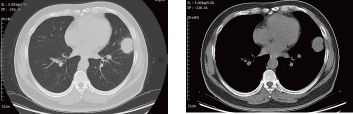

病例概要:患者,男性,50岁,主因“发现左肺上叶占位性病变2月余。”来诊。患者自诉2月前体检胸部CT,发现左肺上叶舌段实性占位,大小约2.5*2.3cm,与胸膜相连,可见分叶、毛刺,恶性可能性大,有咳嗽、咳痰,白痰为主,偶有黄痰,无痰中带血等异常,未采取治疗,定期复查。2周前再次复查胸部ct:左肺上叶占位性病变较前增大,侵犯下叶背段,大小约4.1*3.1cm,考虑肺癌可能。胸外科副主任医师胡晓丹在充分了解患者病情及影像检查后,指示病灶为实性结节且肿物增长过快,需完善全身检查明确有无肿瘤转移可能,后迅速完善全身PET-CT,发现左肺高代谢肿物位于左肺舌段及左下肺内前基底段,病变跨越斜裂胸膜(大小4.6*4.4,SUVmax9.1),恶性可能性大;纵隔、左肺门、右侧内乳区淋巴结转移瘤可能(大者短径1.6cm,SUVmax4.7)。考虑患者淋巴结转移瘤可能性大,需尽快明确病变淋巴结性质,给予经支气管超声内镜纵隔淋巴结穿刺活检术(EBUS-TBNA),胡晓丹会同胸外科医师赵洋乐顺利穿刺4R、4L区、7区、10L淋巴结,术后病理均未见肿瘤细胞,初步考虑淋巴结肿大为良性病变。但为明确肺部占位是否为恶性肿瘤,还需行CT引导下经皮肺病损穿刺活检术明确病变性质,术中操作顺利,无气胸、咯血等异常;术后穿刺病理:(左肺上叶结节)肺脓肿。最终诊断:肺脓肿,在给予2周规范消炎、化痰等治疗后,再次复查胸部CT,病灶大小较前明显缩小(约2.7*3.3cm),实性成分较前明显减少,最终避免了全麻手术切除,顺利出院。

术前胸部CT-肺窗 纵膈窗